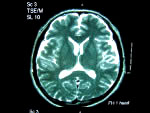

MRIとは

磁気の共鳴を利用した検査装置で、受信する信号を選択することにより、応用の効いたさまざまな映像が鮮明な画像で得られます。また、これまでのようなX線被爆や造影剤による副作用の心配がまったくありません。自覚症状はないが、検査の結果「血管が詰まり、その周辺の組織が壊死したあとが認められる」という、いわゆる無症候性脳梗塞の発見に大きな効力を発揮しています。 |